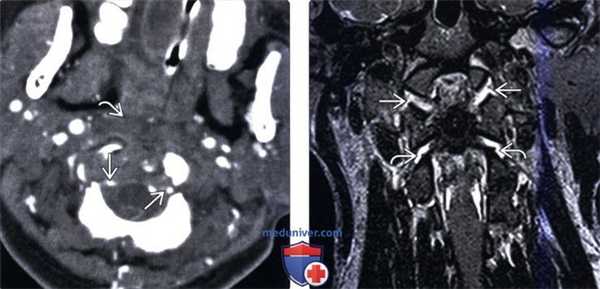

(Слева) КТ-ангиограмма, аксиальная проекция: изменение контура и сужение обеих позвоночных артерий. Здесь также видны признаки отека превертебральных мягких тканей. Сосудистые изменения могут варьировать от вазоспазма и расслоения стенки сонных и позвоночных артерий до полного их пересечения с экстравазацией контраста.

(Справа) Т2-ВИ, фронтальная проекция: расширение суставных щелей АЗС и атланто-аксиальных суставов (ААС) с обеих сторон. Механизмом травмы является гиперэкстензия АЗС и гиперфлексия ААС, что позволяет объяснить такой комбинированный характер повреждения.